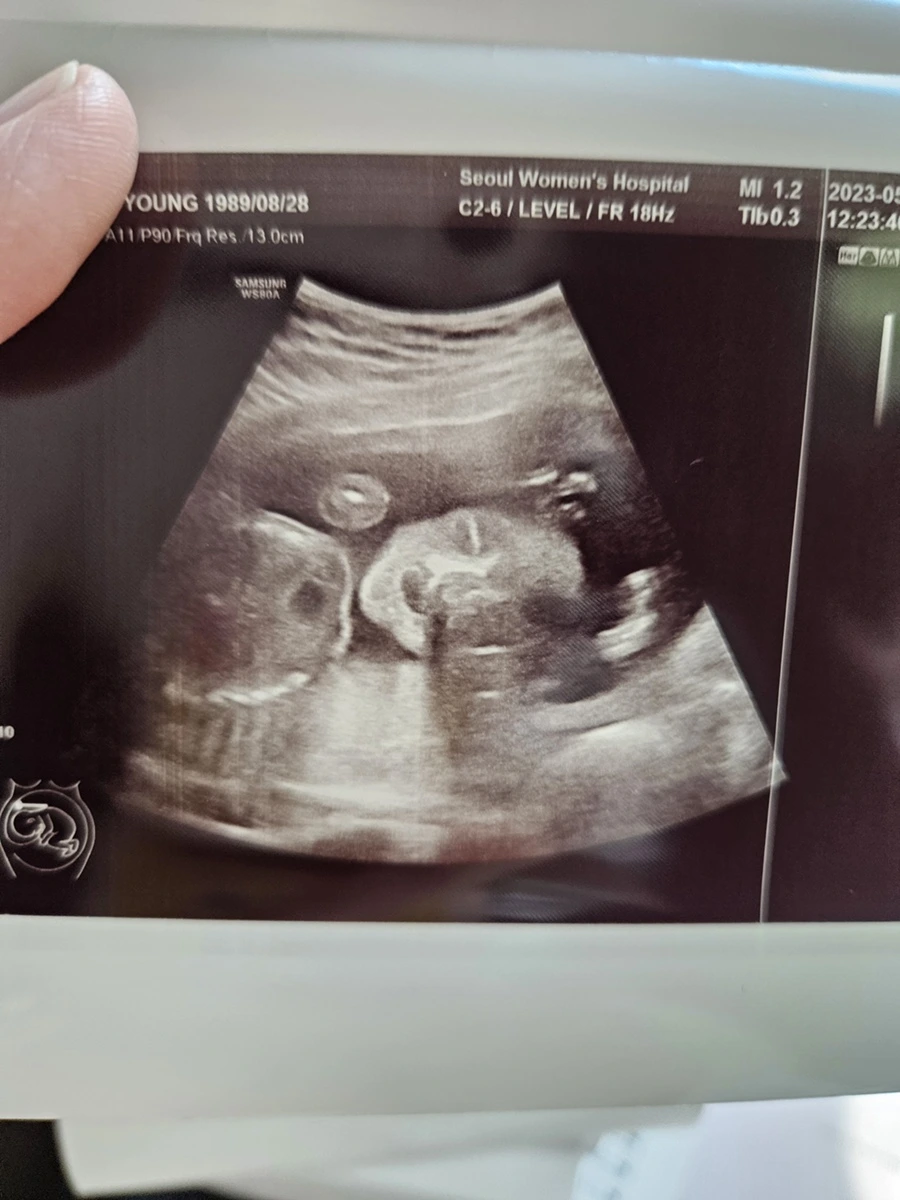

신기하다. 양 손을 머리 위로 올리고 있는 아기 & 아기의 손가락

이전에 짧게 짧게 머리둘레, 배 등 간단히 보던 초음파와 다르게 영상 속에서 아기가 활발하게 움직이는 모습과 얼굴까지 포착되니 남편과 나는 정말 신기했다. 뱃속에서 아기가 다섯개의 손가락과 다섯개의 발가락 뿐만 아니라 포즈를 취하면서 놀고 있는 모습을 본다는 것이 정말 생경한 경험이었다.